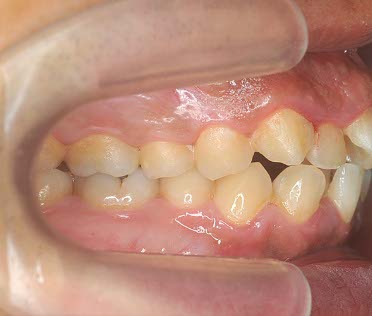

初診相談後、治療をご希望される場合は、初診検査を実施します。この検査で、患者様の現在の口腔内の状態を確認します。

顔貌・口腔内写真の撮影

レントゲン撮影

歯型の模型採取